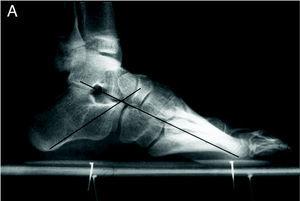

El pie normal es aquel en cuyo fotopodograma A-A' es igual a 2 B-B' (fig. 1). El ángulo de Moreau-Costa-Bartani tiene unos valores de 120-130o y el ángulo astragalocalcáneo (ángulo de Kite) de 15-20o en las proyecciones radiográficas de perfil y dorsoplantar, respectivamente (fig. 2). Los arcos longitudinales del pie van decreciendo progresivamente de 18 a 25o para el primer radio hasta 5o para el quinto radio (fig. 3). En el pie cavo y plano todos estos pará metros están alterados. Aun así, pequeñas alteraciones en estos grados, en ausencia de sintomatología, no pueden considerarse patológicas.

Figura 2. Pie normal: ángulo de Moreau-Costa-Bartani y ángulo astragalocalcáneo.